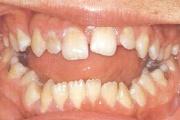

ruumipuudus eesmiste hammaste osas